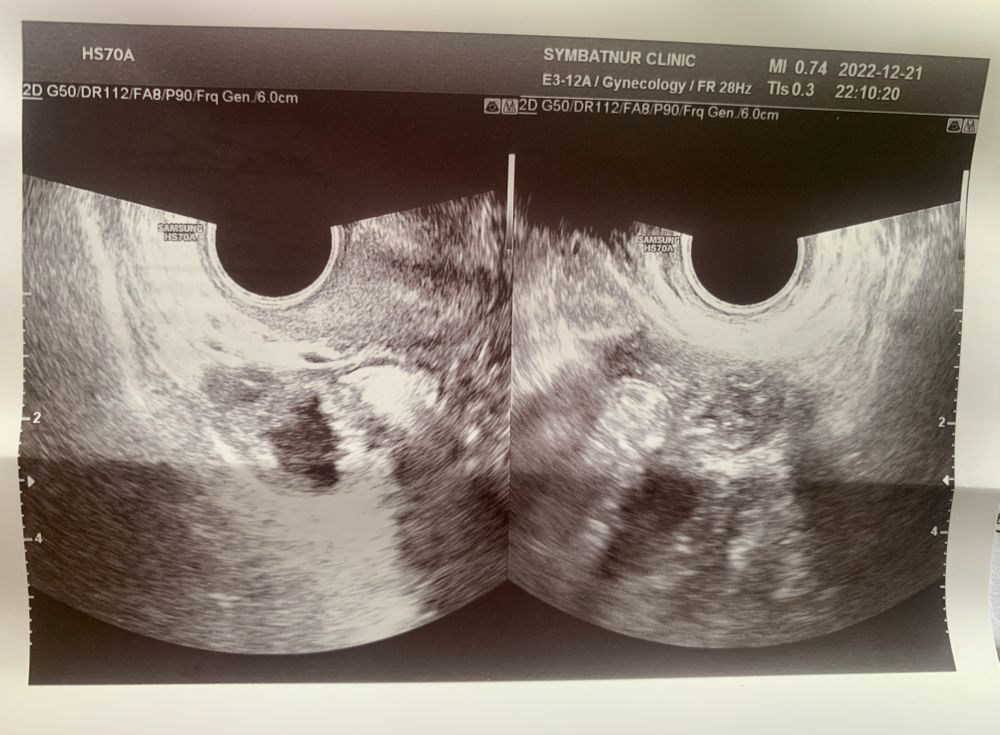

Вчера была у гинеколога 16ДЦ, по узи сказали что хорошая овуляция, 2 желтых тела, пить дюфастон 10 дней. Помогите пожалуйста расшифровать заключение узи

Структурных изменений нет, эндометрий трехслойный, 2 жт ( про размеры : кажется что в кисту хотят уйти...то которое 30мм так точно не остановится в размерах как по мне), шейка сомкнута, вроде все